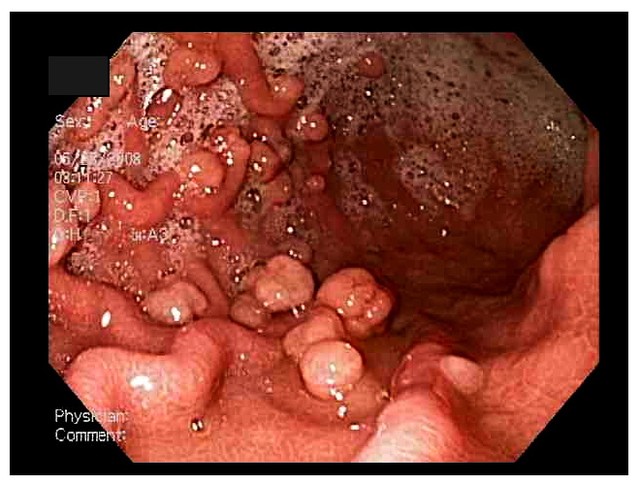

VBF-Ung thư dạ dày là một trong những loại ung thư khó phát hiện nhất.Quan trọng nhất vẫn là chúng ta phải luôn chú ý tới những biểu hiện lạ của cơ thể để mà kịp thời đi khám bệnh.Polyp dạ dày, còn gọi là khối y dạ dày, là khối tế bào hình thành bên trong lớp lót dạ dày.

Nguy cơ trở thành ung thư của khối u tăng sản là rất nhỏ, nhưng những khối u có đường kính lớn khoảng 2cm trở lên thì có nguy cơ trở thành ung thư.Hình ảnh polyp dạ dày thông qua nội soi dạ dày.